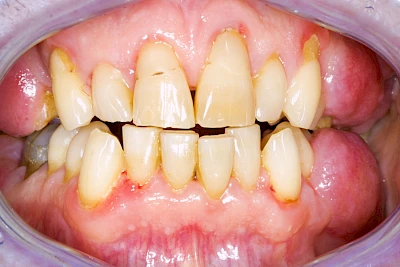

Bakterien in den Zahnbelägen greifen neben den Zähnen auch das Zahnfleisch (Gingiva) und den gesamten Zahnhalteapparat (Parodont) an. Der Körper reagiert mit einer Entzündung, sichtbar als Rötung und Schwellung. Meist blutet das Zahnfleisch z .B. beim Essen oder auch beim Putzen der Zähne.

Ist zunächst nur das Zahnfleisch von der Entzündung betroffen, spricht man von Gingivitis. Später, wenn auch der Knochen um die Zähne herum entzündet ist, spricht man von einer Parodontitis. Bei der Parodontitis wird der Knochen nach und nach abgebaut und das Zahnfleisch zieht sich zurück. Die Zahnhälse und Zahnwurzeloberflächen liegen mehr und mehr frei. Die Zähne werden zunehmend lockerer und fallen schließlich aus.